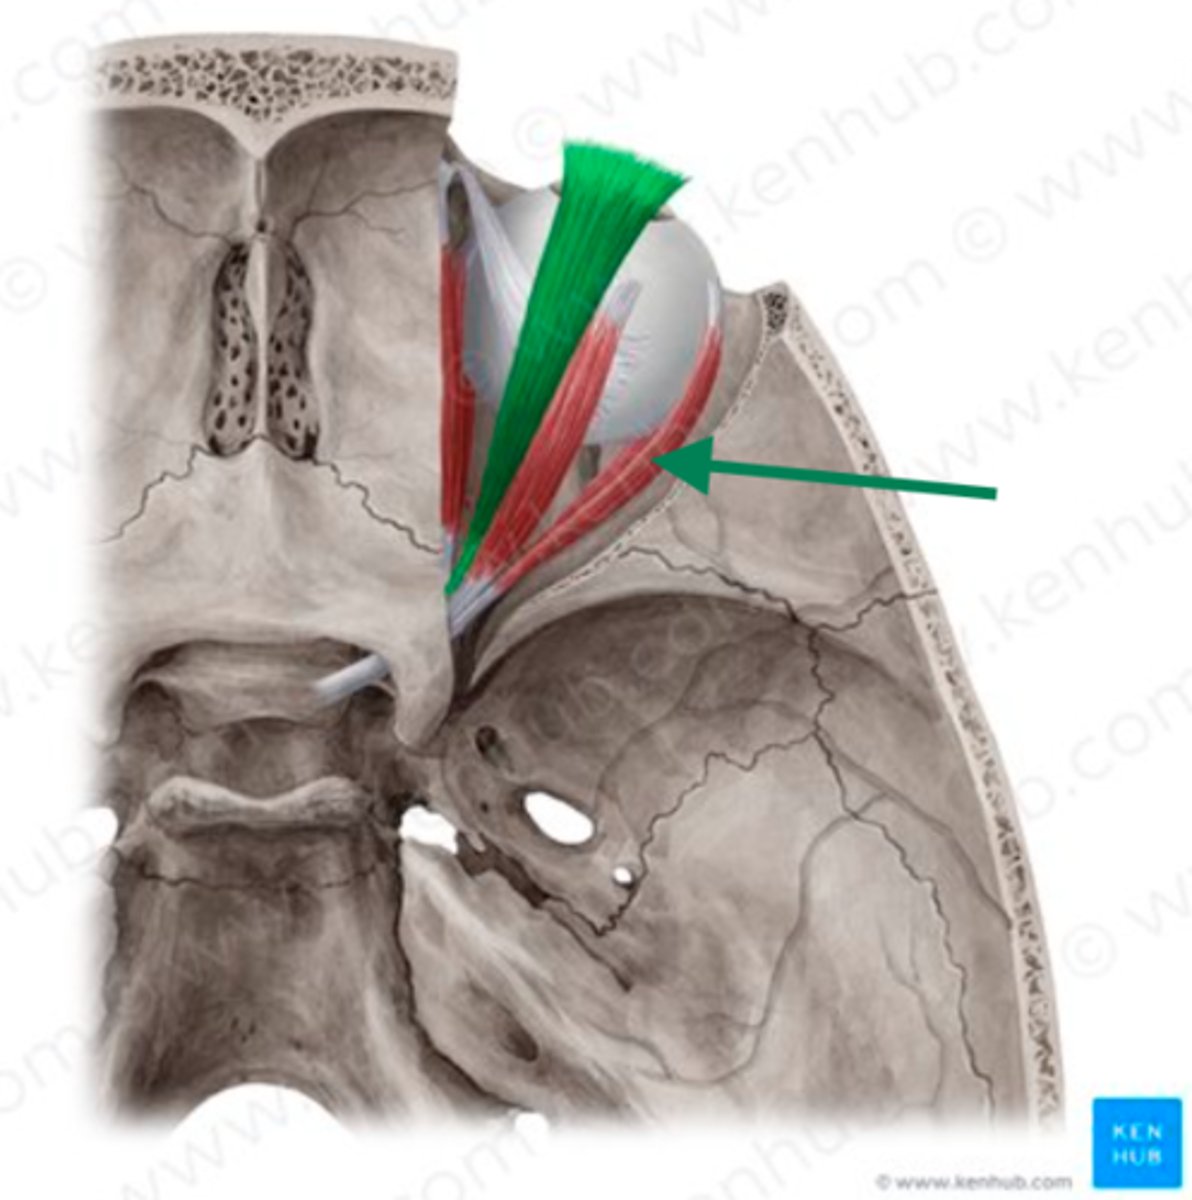

levator palpebrae superioris

superior rectus

lateral rectus

superior oblique

superior rectus